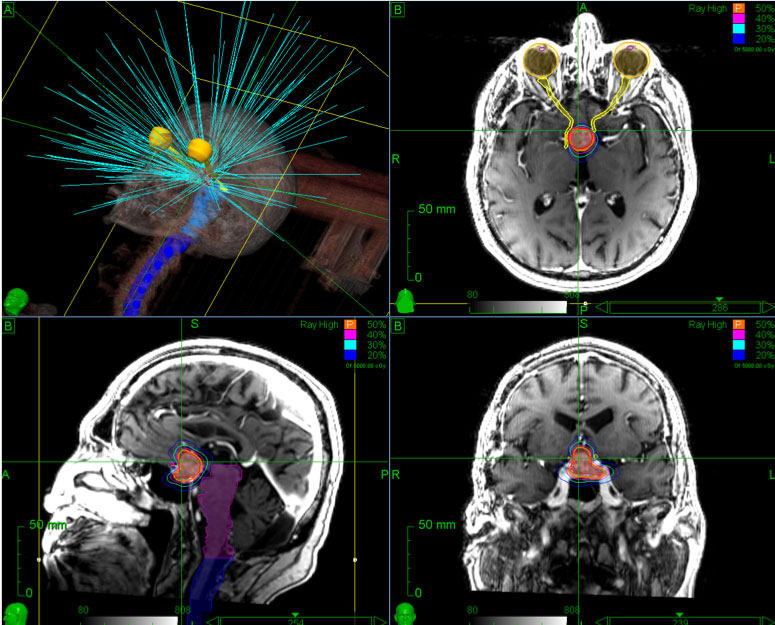

Brain Srs With Cyberknife Accuray